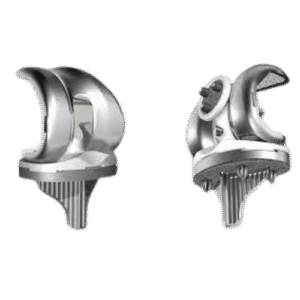

Reemplazo

articular

Artroplastia de rodilla y cadera para restaurar movilidad y aliviar dolor en articulaciones dañadas.